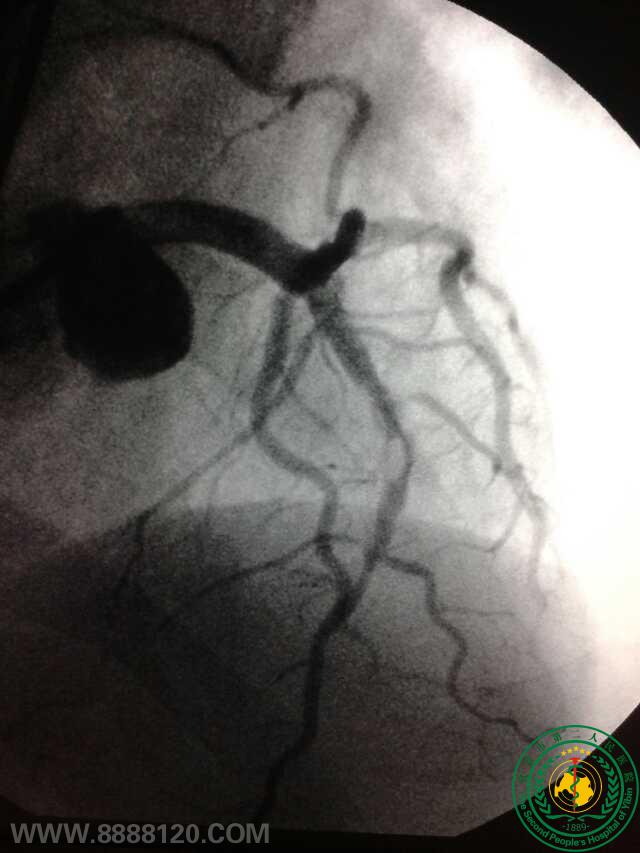

冠脉治疗新技术——宜宾首例冠脉旋磨术

冠脉治疗新技术——宜宾首例冠脉旋磨术6772